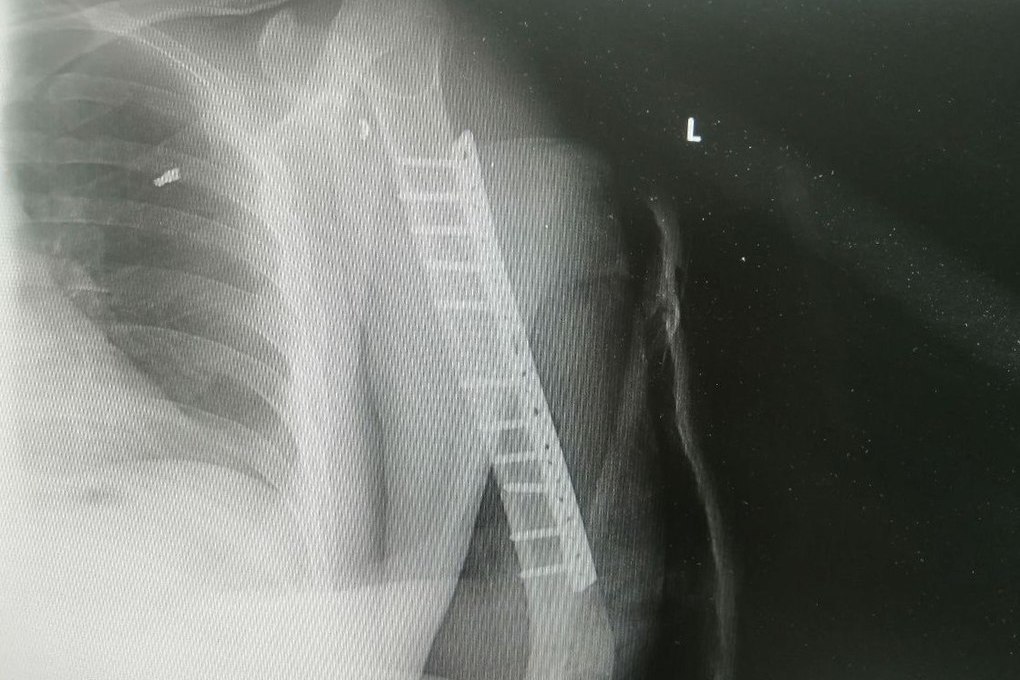

Фото Сургутской травматологии

39-летний мужчина с минно-взрывной травмой вскоре сможет спокойно двигать рукой. Благодаря слаженной работе бригады врачей Сургутской травматологии мужчина получил такую возможность. Об этом сообщается в telegram-канале медучреждения.

Обследование пациента выявило повреждение лучевого нерва. Чтобы исправить ситуацию, нужно было пересадить аутотрансплантат. Для этого в микрохирургической операции понадобились несколько врачей.

Травматологи-ортопеды Владимир Кельметр и Алексей Котов оперировали пациента более четырех часов. В ближайшие две недели пациента будут наблюдать.